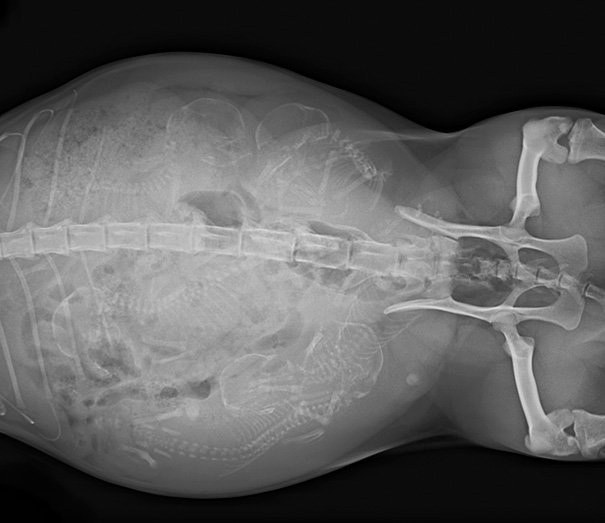

Итак, как выглядят рентгеновские снимки беременных животных:

морская свинка